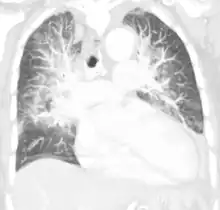

Pulmonary edema on CT-scan (coronal MPR)

Low oxygen saturation in blood and disturbed arterial blood gas readings support the proposed diagnosis by suggesting a pulmonary shunt. A chest X-ray will show fluid in the alveolar walls, Kerley B lines, increased vascular shadowing in a classical batwing peri-hilum pattern, upper lobe diversion (biased blood flow to the superior parts instead of inferior parts of the lung), and possibly pleural effusions. In contrast, patchy alveolar infiltrates are more typically associated with noncardiogenic edema[3]